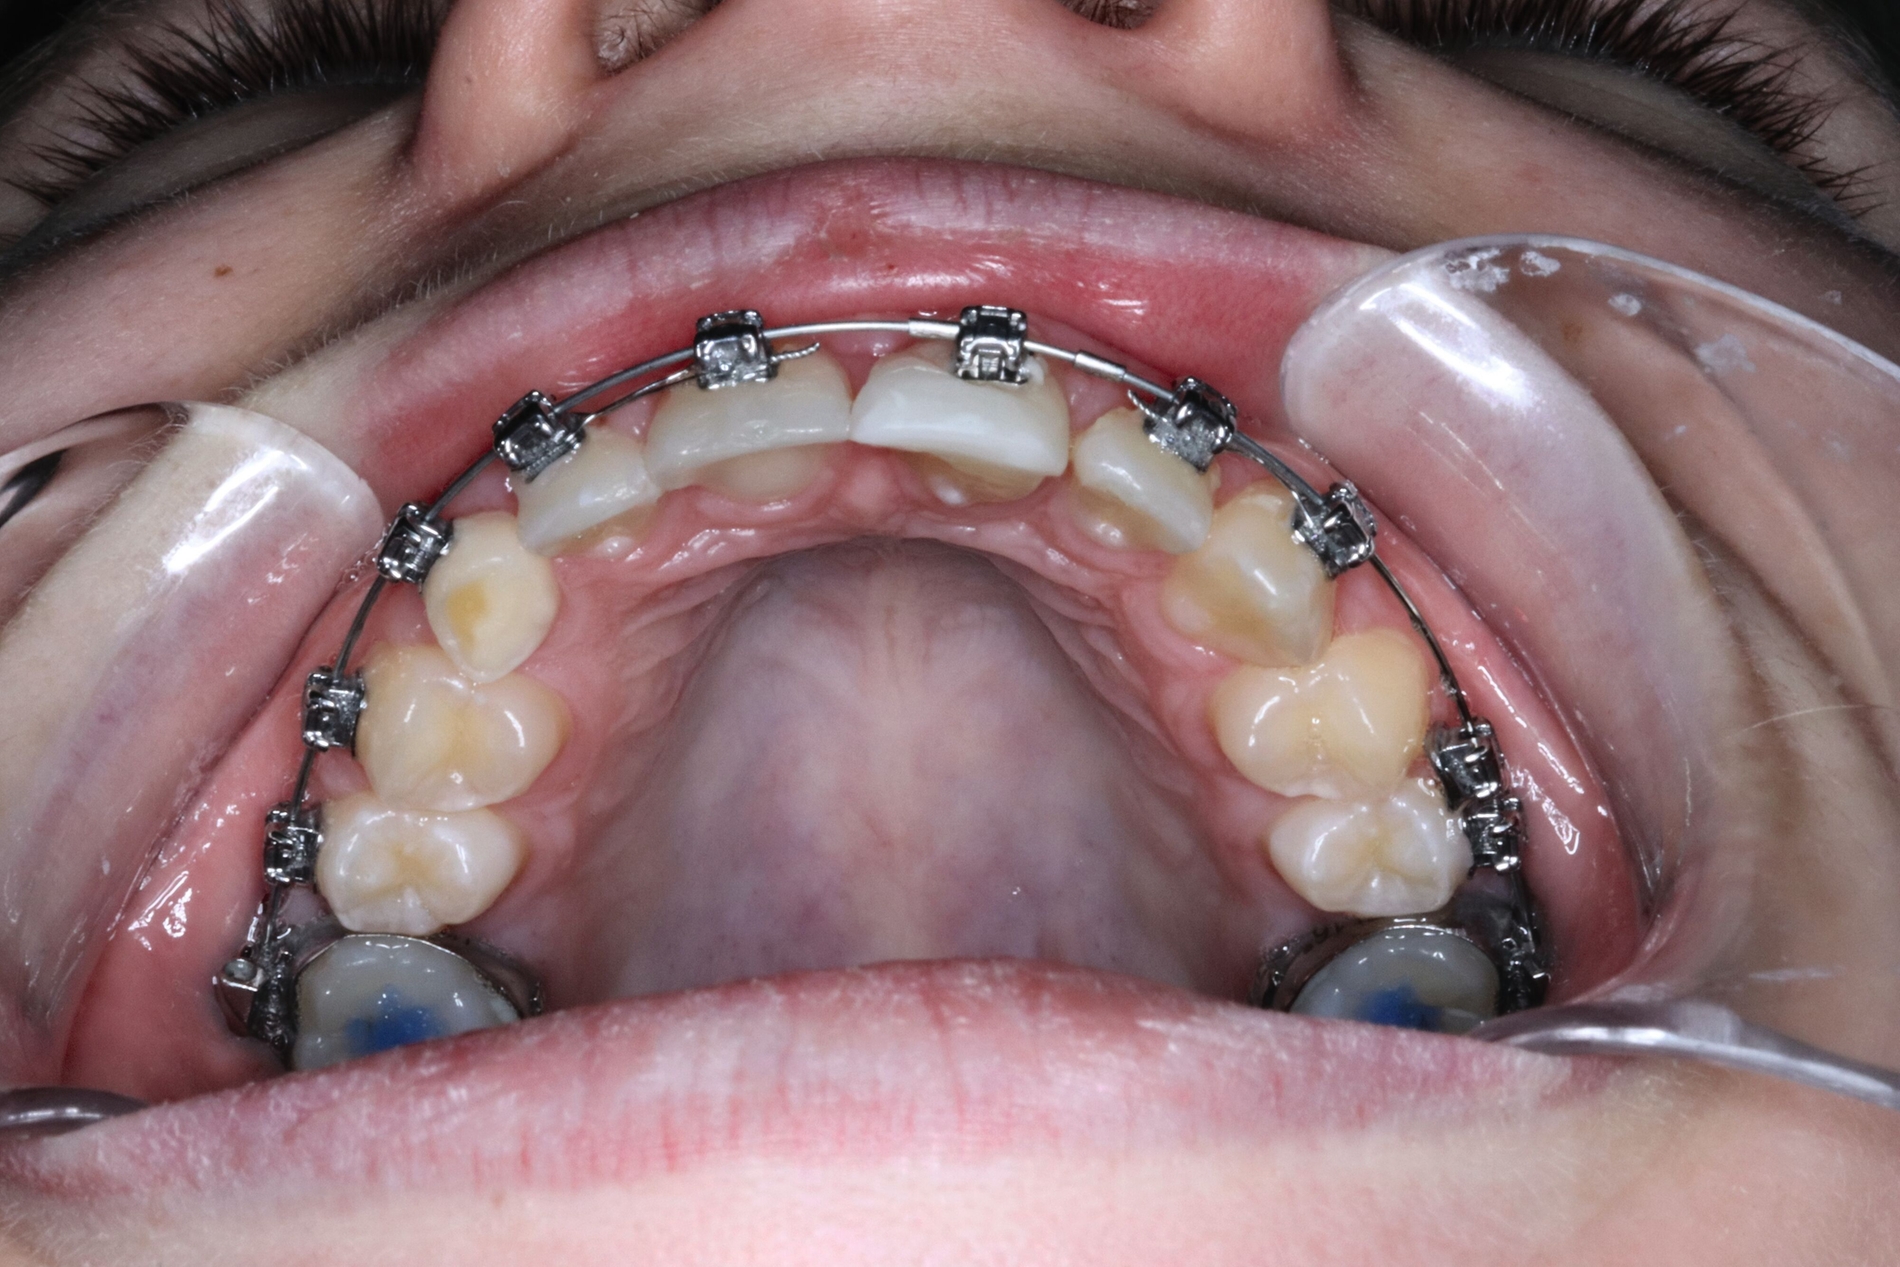

Auf Empfehlung des mitbehandelnden Kieferorthopäden sollte der natürliche Lückenschluss in regio 53 belassen und die autogene Transplantation des verlagerten Eckzahns 13 an die Stelle des verloren gegangenen Zahnes 21 durchgeführt werden. Der Eckzahn 13 wurde etwa einen Monat später in die Region 21 transplantiert und am zuvor eingebrachten kieferorthopädischen Bogen kunststoffadhäsiv fixiert (Abbildung 4).

Der spätere kunststoffadhäsive Aufbau des Zahnes erfolgte nach Erreichen des isogingivalen Niveaus im Vergleich zum Nachbarzahn 11 durch kieferorthopädische Extrusion (Abbildung 5).

Ein Jahr später präsentiert sich das Transplantat in regio 21 reizfrei und perfekt in Okklusion stehend. Die Transplantation des verlagerten Eckzahns an die Stelle des Zahnes 21 war mit einer ausgezeichneten Wiederherstellung der knöchernen und weichgewebigen Situation verbunden (Abbildung 5).